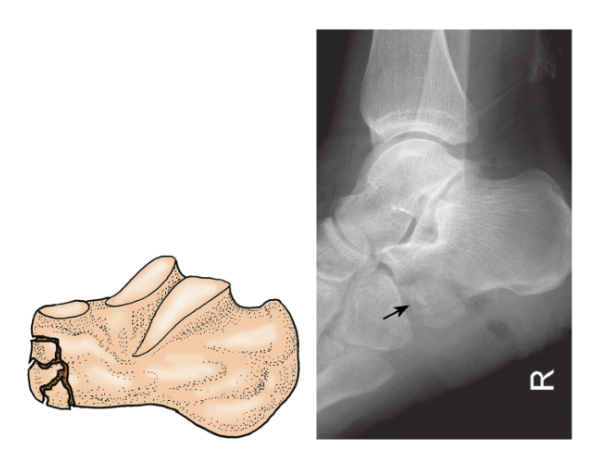

1、跟骨前突骨折:

两种不同损伤机制引起跟骨前突骨折。

(1) 跟骨前突撕脱骨折:

多见,常由足跖屈、内翻应力引起。暴力引起附着在跟骨前突及足舟骨、骰骨近端的分歧韧带紧张,造成跟骨前突撕脱骨折。骨折线伸入跟骰关节,骨折块较小,典型的情况下包含极少量的关节面(图5)。

图5 跟骨前突撕脱骨折